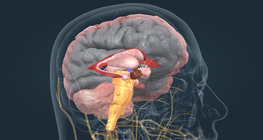

Understanding the building blocks of the nervous system.

The nervous system: anatomy and function.

A case study of a patient admitted to the neurology ward, from history taking to nursing care.